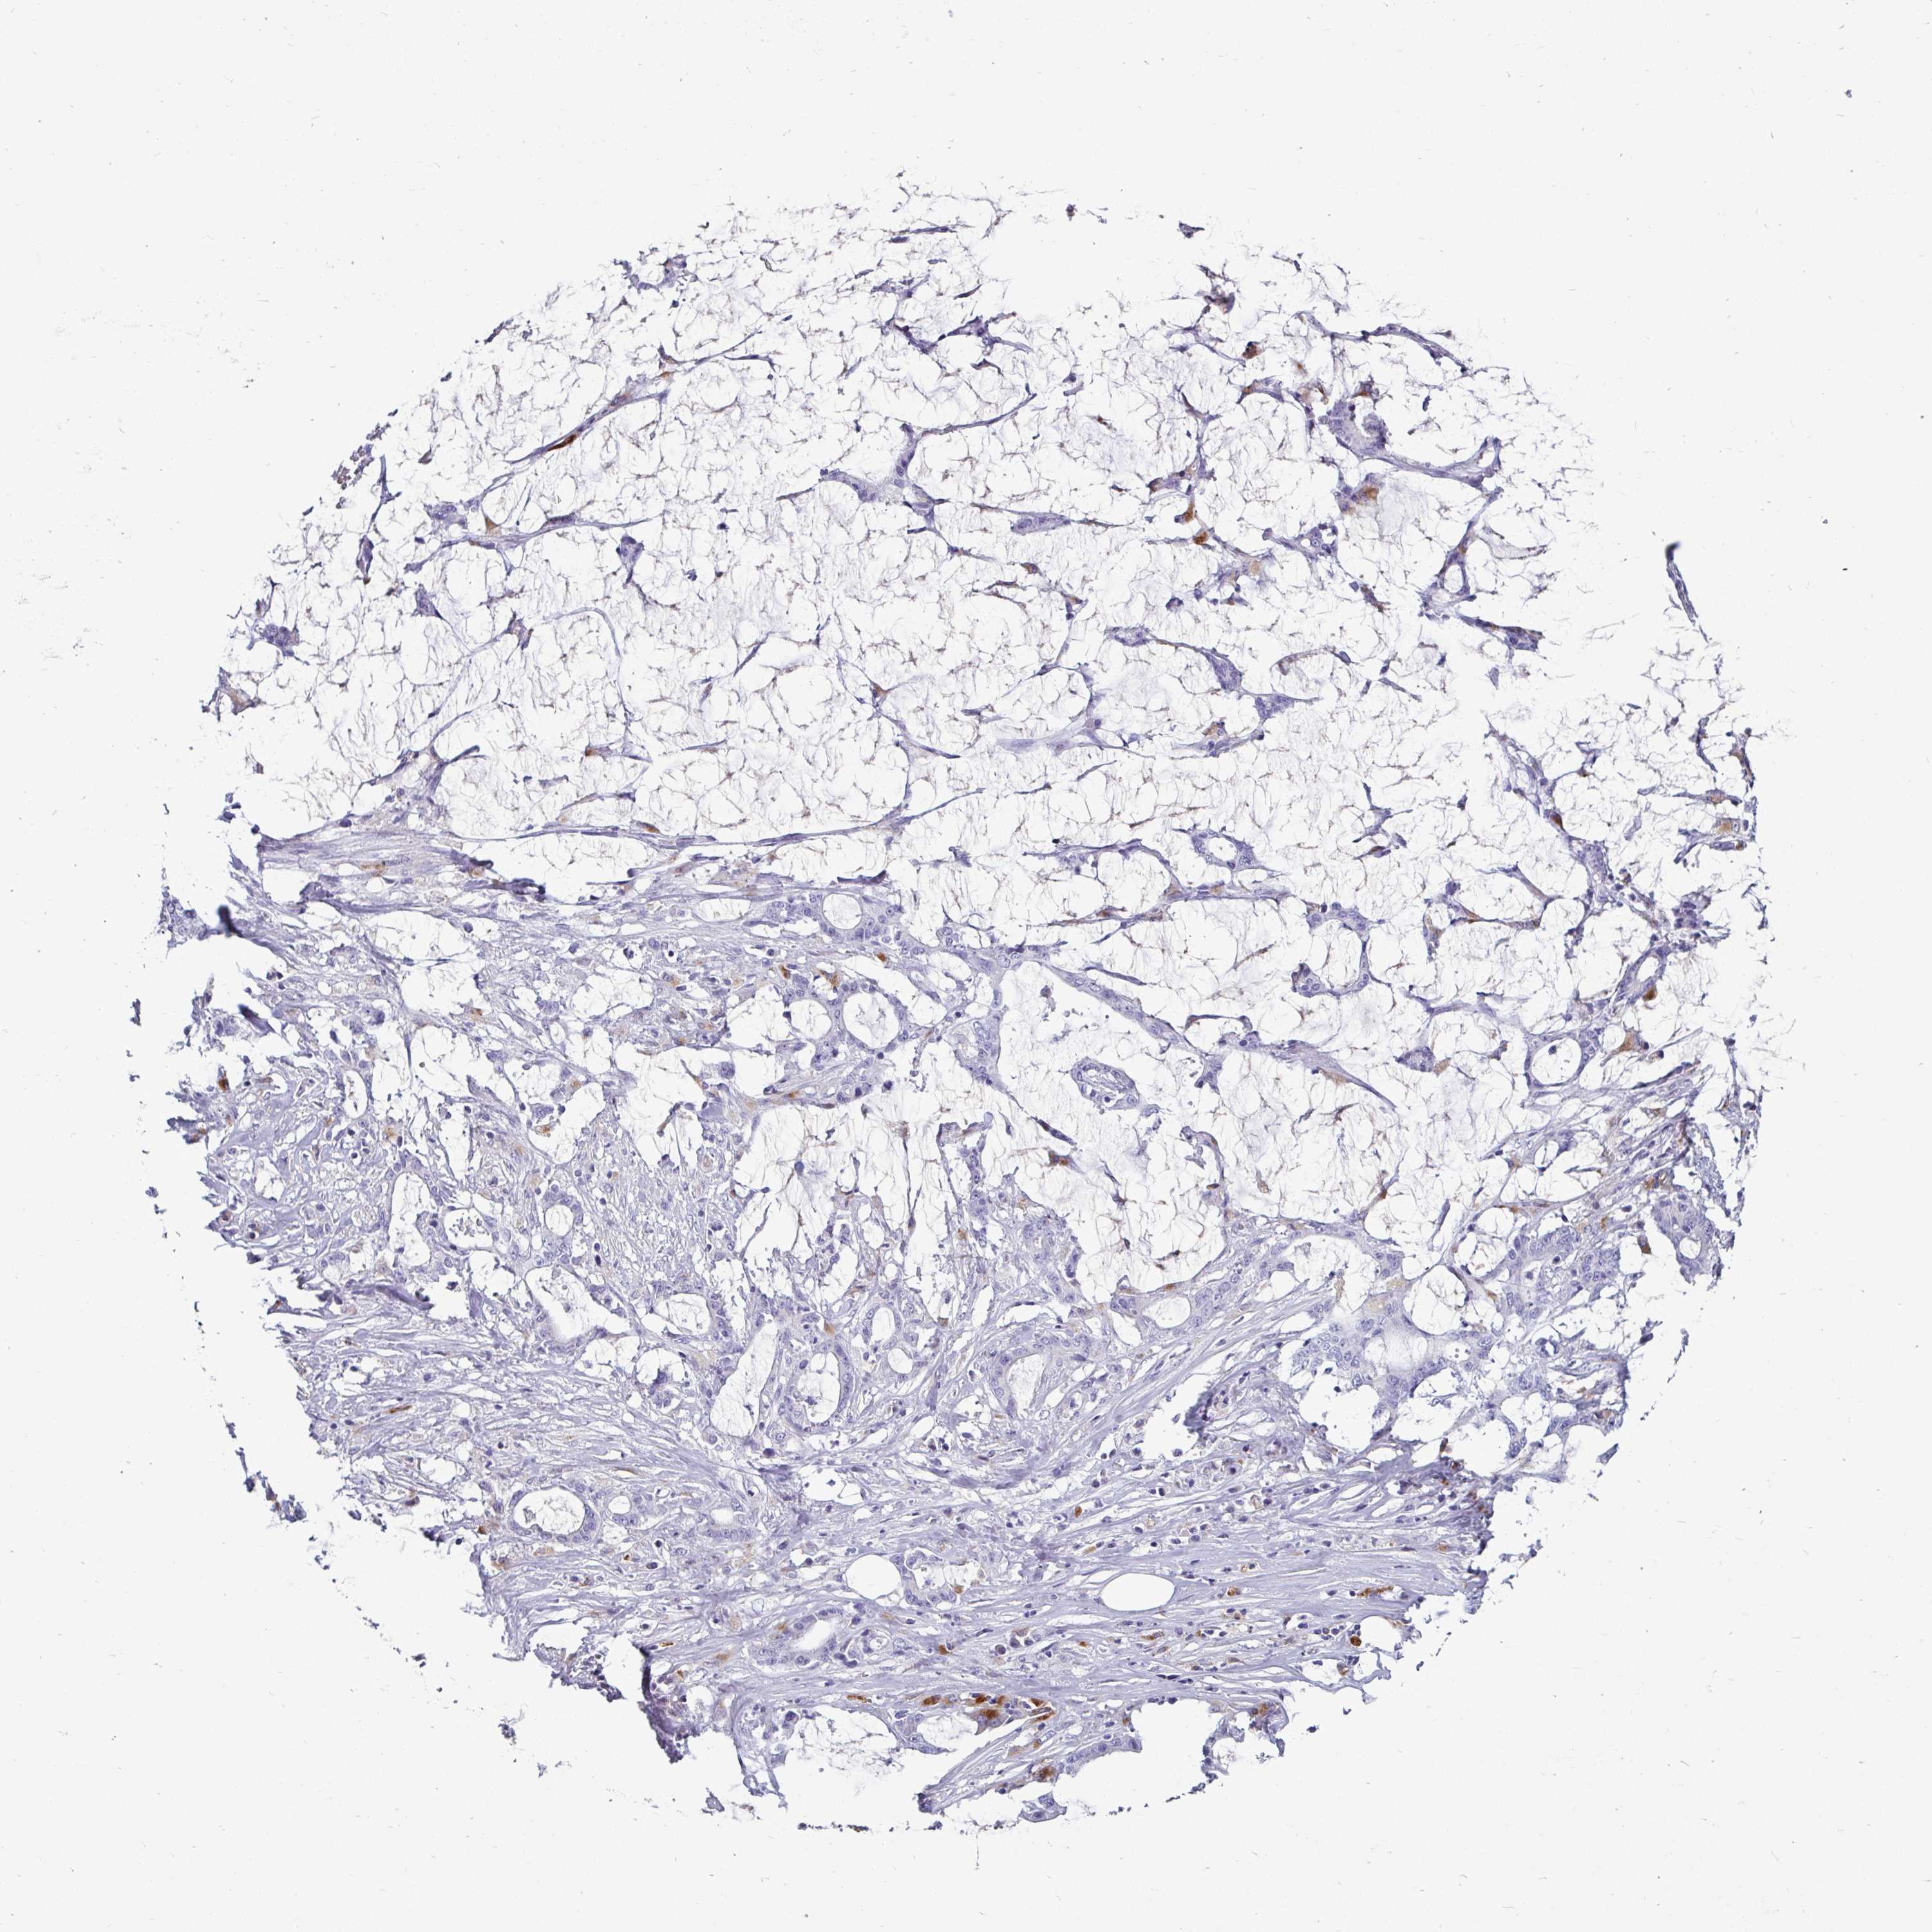

STOMACH CANCER - Protein expressioni

A mouse-over function shows sample information and annotation data. Click on an image to view it in a full screen mode. Samples can be filtered based on level of antibody staining by selecting one or several of the following categories: high, medium, low and not detected. The assay and annotation is described here.

Note that samples used for immunohistochemistry by the Human Protein Atlas do not correspond to samples in the TCGA dataset.

Antibody stainingi

Antibody staining in the annotated cell types in the current human tissue is reported as not detected, low, medium, or high, based on conventional immunohistochemistry profiling in selected tissues. This score is based on the combination of the staining intensity and fraction of stained cells.

Each image is clickable and will lead to virtual microscopy that enables deeper exploration of all samples and also displays staining intensity scores, fraction scores and subcellular localization as well as patient and tissue information for each sample.

Antibody HPA049876

Antibody HPA053504

Antibody CAB025114

Staining

High

Medium

Low

Not detected

Intensity

Strong

Moderate

Weak

Negative

Quantity

>75%

75%-25%

<25%

None

Location

Nuclear

Cytoplasmic/membranous

Cytoplasmic/membranous,nuclear

Adenocarcinoma, NOS